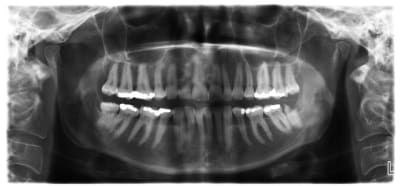

Patiente 50 ans, aucun pb de sante qui est partie aux urgences en cours d extraction de 38 chez son dentiste.

Situation anatomique exceptionnelle, elle se baladait le long du Canal mandibulaire et venait flirter en distal de la 38.

Pas sur qu'un cone beam l'aurait mise en évidence.

Si le cbct l a mise en evidence par le radiologue dentaire, mais c est vraiment exceptionnel 1/10000